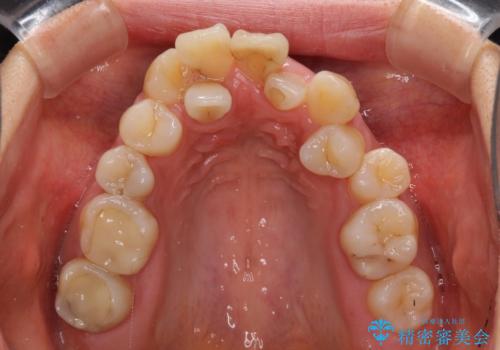

骨格的に上顎は狭く、下顎は右側にシフトしていたため、右側臼歯はクロスバイトとなっていました。

上顎骨を急速拡大装置により拡大し、ワイヤー装置による抜歯矯正治療を行うこととしました。